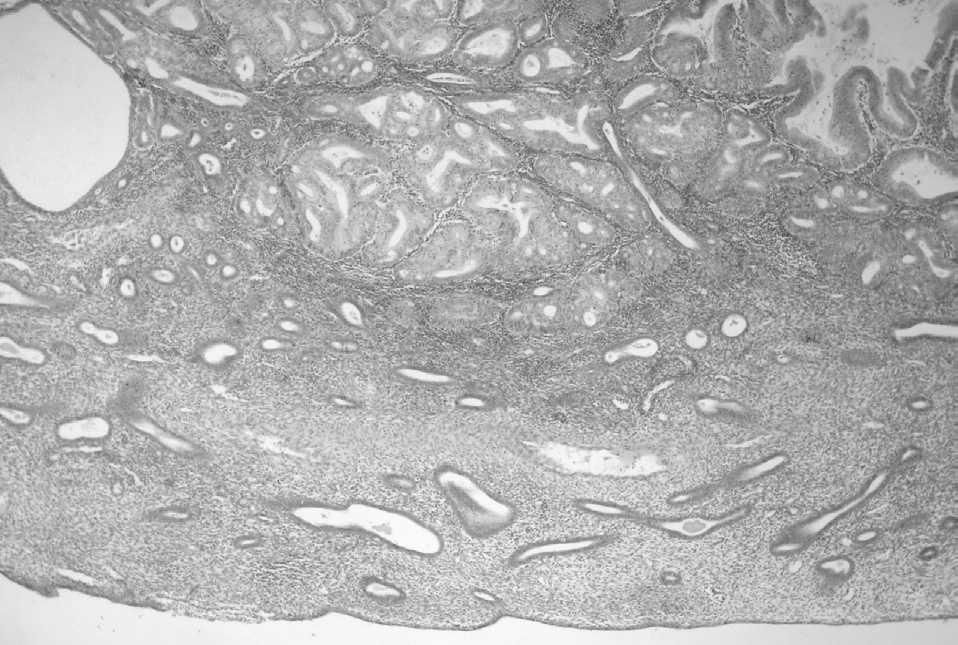

En 4 pacientes el diagnóstico de pólipo con adenocarcinoma se efectuó en una biopsia y en las otras 2 en la pieza de histerectomía, pues en ambas la biopsia previa reveló un adenocarcinoma sin criterios morfológicos de pólipo (tabla 2). El tipo histológico fue siempre endometrioide, y en el caso 1 se apreciaban focalmente algunas áreas serosas. El grado histológico según la FIGO fue G1 en 4 casos y G2 en los 2 restantes. El tamaño medio de los pólipos fue de 2,6 ± 1,7 cm (rango: 0,8-2,6) y en todos ellos la afectación por parte del adenocarcinoma era parcial; es decir, siempre se identificaron áreas de pólipo endometrial convencional conservadas. El tamaño medio de las neoplasias fue de 1,5 ± 0,6 cm (rango: 0,3-2). El cáncer se localizaba en la periferia del pólipo en 4 casos (fig. 1) y en la región central en 2 (fig. 2). En uno de los 2 casos en los que la lesión se encontraba en la porción central del pólipo existía afectación neoplásica del margen de resección. Sólo en uno de los casos se constató permeación tumoral de vasos linfáticos del pólipo.

Figura 1.Adenocarcinoma endometrioide situado en la porción periférica de un pólipo endometrial. Se observan glándulas no neoplásicas y vasos con paredes engrosadas (caso 3).